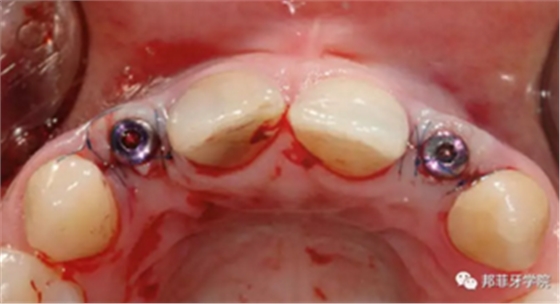

采用手術導板進行備洞及植入,植入扭矩35Ncm。植體適當偏腭側植入,避免鄰近結構破壞及前庭處骨外壁穿孔。植體肩臺位于鄰牙釉牙本質界根尖方2mm(圖7&8)。

圖7 & 8:導板下備洞及植入

牙齦成型器周圍應嚴密縫合,防止唾液進入切口(圖9)。X線片顯示植體位置理想(圖10)。愈合期未見并發(fā)癥,植體周圍牙齦愈合良好(圖11)。十周后取模,椅旁制備臨時牙(圖12),并制作螺絲固位PEEK基臺。

圖 9:上牙齦成形器并嚴密縫合